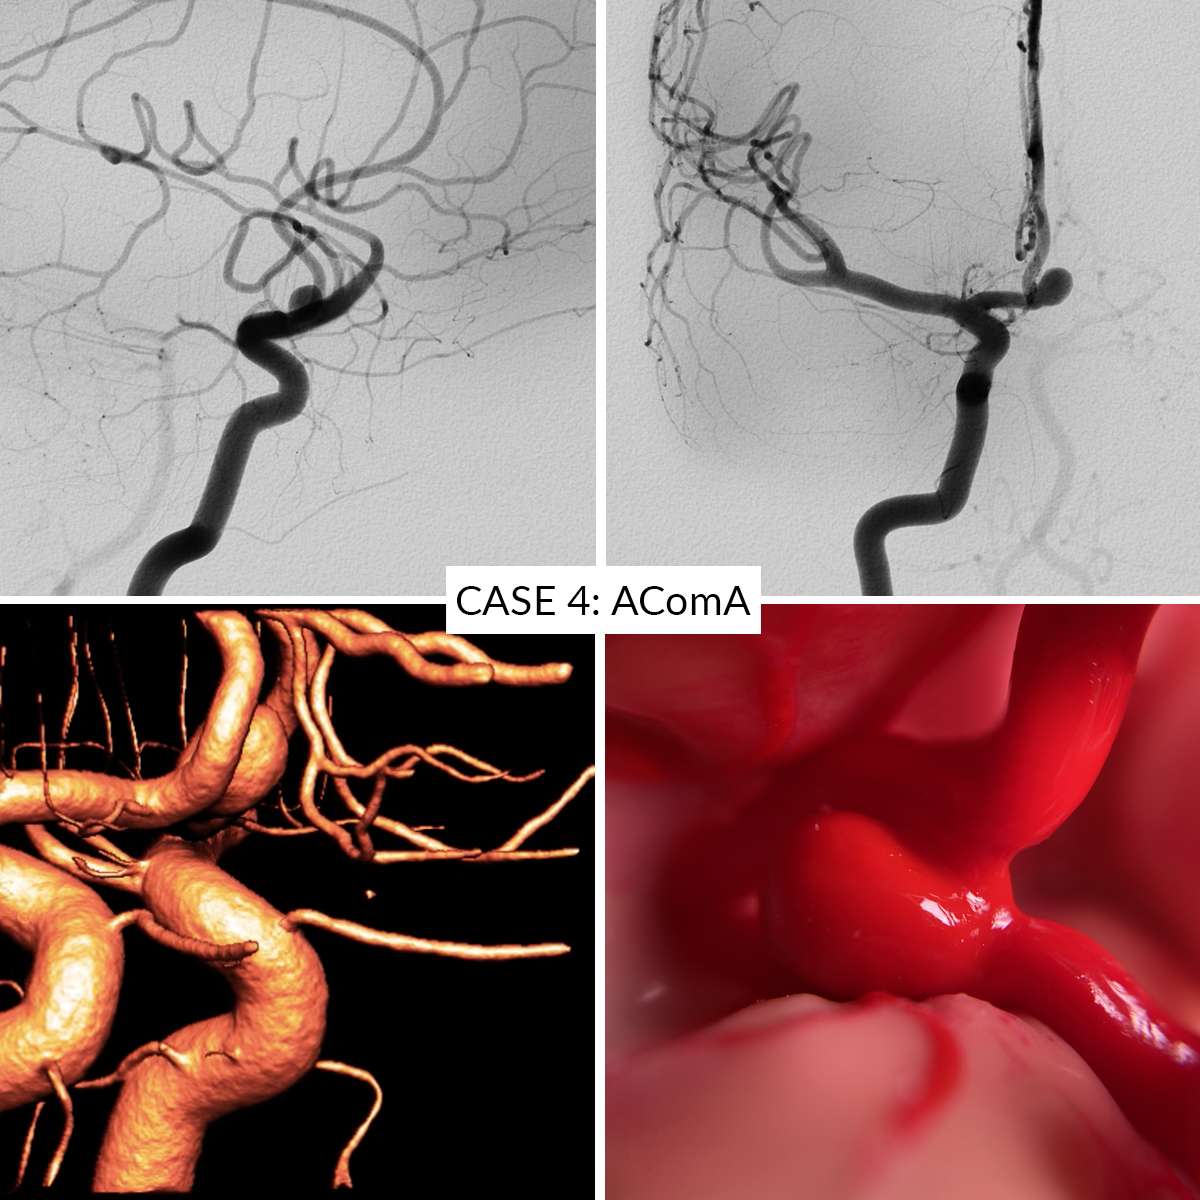

Case 4 : Anterior Communicating Artery

In the AneurysmBox simulator you can operate 5 different aneurysm cases:

- Case 4: Anterior Communicating Artery

Aneurysms are clippable unlimited number of times. Remove the clips gently to avoid damaging the aneurysms.